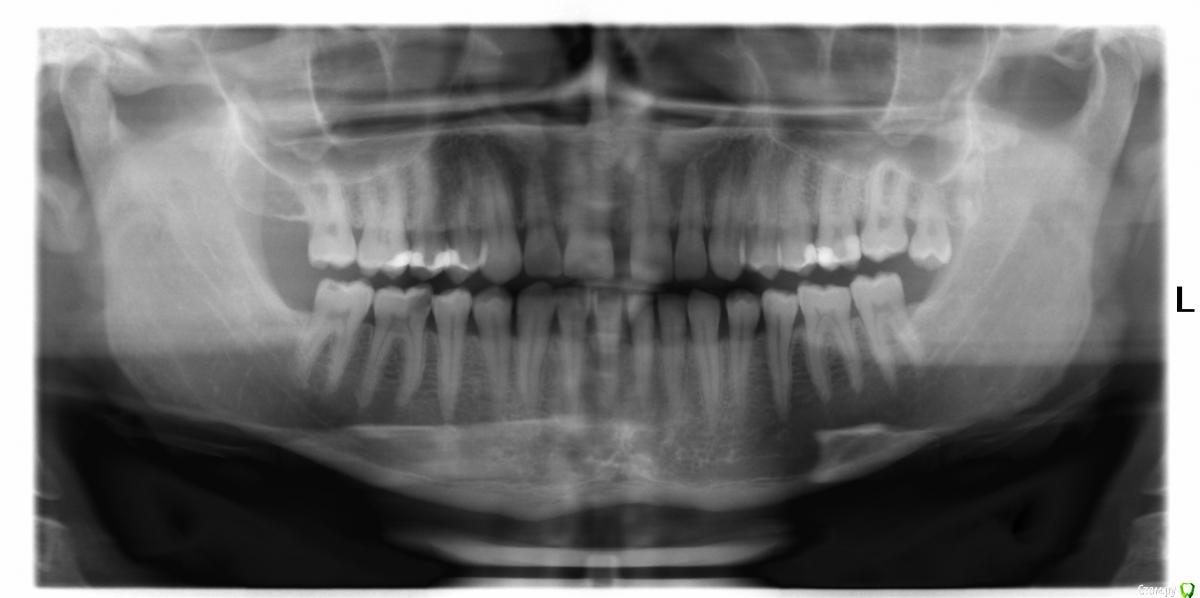

lohudra Опубликовано 22 сентября, 2016 Поделиться Опубликовано 22 сентября, 2016 (изменено) Здравствуйте! Нужна профессиональная помощь в выборе лечения. Мне сделали снимок, по снимку(правая сторона, низ, предпоследний зуб) видно кариес, около канала, предложили полностью почистить каналы и запломбировать.Вопрос мучает уже неделю, подскажите пожалуйста, надо ли вообще забираться в эти каналы, когда, слева (верх) на снимке тоже видно пломбу возле каналов, но каналы при этом не тронуты?Заранее спасибо! Изменено 22 сентября, 2016 пользователем lohudra Ссылка на комментарий

Ирина Игоревна Опубликовано 22 сентября, 2016 Поделиться Опубликовано 22 сентября, 2016 Лечить кариес необходимо. Судя по Вашему снимку, при удалении некротизированных кариозных тканей большая доля вероятности что будет вскрыта пульпа этого зуба. В большинстве случаев пульпа при таких поражениях уже является инфицированной и будет необходимо ее удаление. Ссылка на комментарий

Ирина Игоревна Опубликовано 22 сентября, 2016 Поделиться Опубликовано 22 сентября, 2016 На верхних же зубах мы видим ситуацию после удаления всех поражённых тканей, пломба стоит близко к нерву, но вскрытия его не произошло, что даёт возможность доктору сохранить зуб витальным и не прибегать к лечению каналов. Ссылка на комментарий

St. Опубликовано 22 сентября, 2016 Поделиться Опубликовано 22 сентября, 2016 А как в моей ситуации, не подскажите? Может тоже будет возможность удаления пораженных тканей, не прибегая к вскрытию каналов? Но по снимку видно что близко к каналам или можно начать, а там по обстоятельству? Еще стоматолог сказал, что после лечения и наложения пломбы, к нему снова приходил пациент с жалобой на боль и тогда приходилось уже вскрывать и чистить каналыВам все правильно сказали. Обычно после анестезии убирают все пораженные кариесом ткани и по ходу смотрят есть ли сообщение с нервом. Если есть - лечат каналы. Если нет - ставят пломбу и наблюдают. Есть риск что может начать болеть, тогда удаляют нервы. Сказать предварительно на 100% как будет никто не может, нужно только открывать и смотреть.Только не затягивайте с лечением. Ссылка на комментарий

St. Опубликовано 22 сентября, 2016 Поделиться Опубликовано 22 сентября, 2016 Не подскажите как смотрят? Глазами и на ощупь)) Но по снимку видно что глубокий кариес? Да Стоматолог сказал, что если убирать кариес, то возможна вероятность и вскрытия канала. Правильно. Кариес убирают до здоровых тканей. И пока не почистили не ясно вскроется "нерв" или нет Ссылка на комментарий